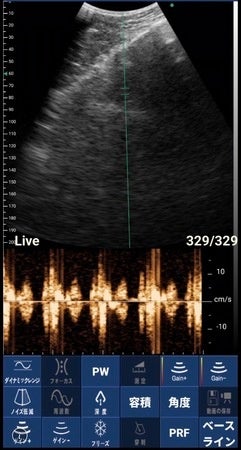

「ポケマム・サウンズ」は、全国の妊婦さんとそのご家族から支持を得る「ポケマムシリーズ」の特長であるスマートフォンでお腹の中の赤ちゃんの姿をリアルタイムに見る機能に加えて、赤ちゃんの心音を聴取する機能(パルスドプラ方式による音波検出)を新たに搭載。胎児の様子を見ながら心音を聴くことにより、成長を実感し妊娠期の不安軽減に繋がる他、一緒にエコーを使用することでパートナー間・家族間のコミュニケーションが増え、妊娠への理解度やサポート向上が期待できます。

・胎児心音の聴取(専用アプリ連携)

・スキャンモード:B、B/M、B+カラー、B+PDI、B+PW

・プローブ周波数:3.2MHz/4MHz

・スキャン深度:90/160/200/240mm

・イメージ調整:BGain、TGC、DYN、フォーカス、深度、ハーモニック、ノイズリダク ション、カラーゲイン、ステア、PRF、フレーム数設定(100/200/500/1000)